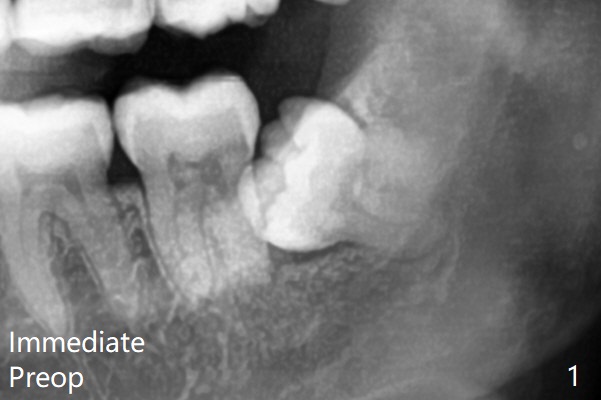

Note bony defects associated with the distal roots of the 2nd molars (red dashed line).